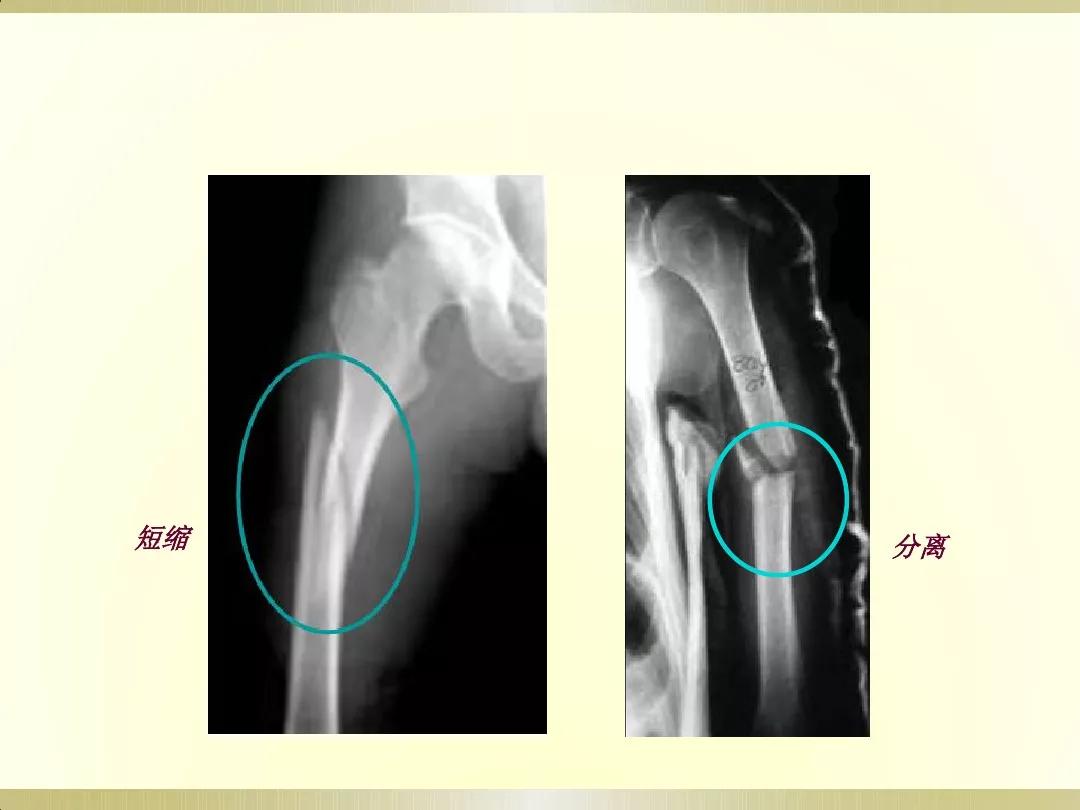

X线摄片就是通过让一种有能量的电磁波,即X射线透射过身体不同组织结构,在胶片上形成明暗或黑白对比不同的影像,被称为X线摄片。

医生可以通过X射线检查来识别各种组织,并根据阴影的形态和浓淡变化来分析其是否属于正常。这很像我们日常所说的拍照片,出来的图像是平面的。

检查部位:X线可以检查身体的许多部位。通常用于检查胸部(大致了解情况)、骨骼、肌肉或脏器,以及发现体内的气体,也可探查金属物体。